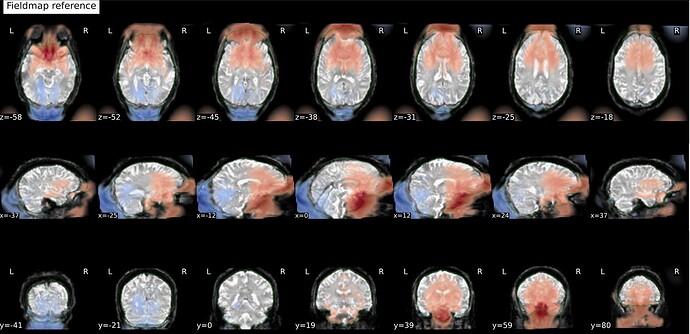

And these are the fmapCoreg_bold images: